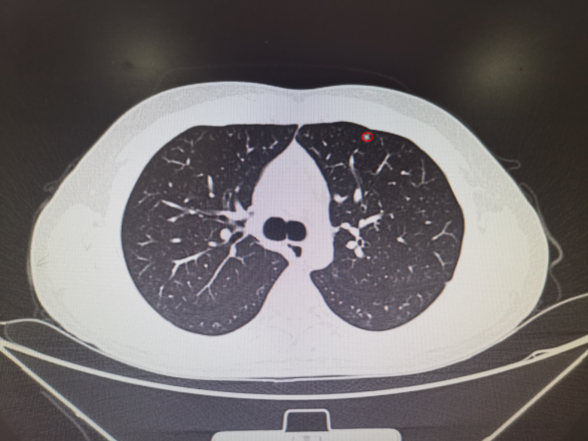

ENB-MWA患者术前小结节位置及消融术后3天复查CT见病灶区域成消融后炎性改变(完全覆盖结节位置)。